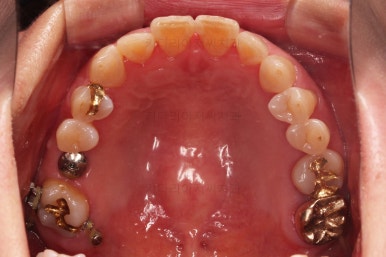

적절한 공간이 확보되었다고 판단되면 임플란트를 식립합니다.

임플란트가 뼈에 단단히 붙을 몇 개월의 시간동안 부산교정치료를 좀 더 마무리 해주고요.

임플란트 머리 부분까지 완성이 되었어요.

교정치료와 임플란트치료를 병행해서 치아 빠진 부위가 다행히 잘 마무리가 되었네요.